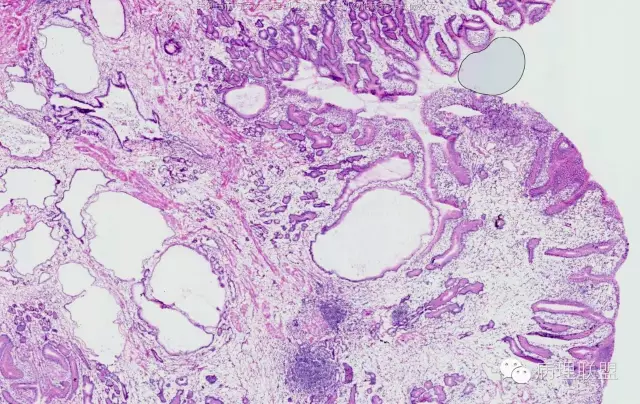

男,58岁,胃窦2.5×2.1×1.5cm大小肿物。冰冻切片。(病例由南方医科大学 邓永键教授提供,致谢!)

平滑肌束进入病变中,重点是表面腺体与正常腺体类似。

错构瘤性息肉/Peutz-Jephers息肉,在胃体,表面腺体是胃体腺,胃窦部是粘液腺;在小肠、大肠,表面腺腺体是小肠腺、大肠腺。该病变可以从食管至肛门都可发生。如果不出现出血、溃疡、梗阻症状,不体检,病人不会出现症状,不易被发现。小肠发生,易致肠梗阻、肠扭转。肛门发生,可脱出似内痔。